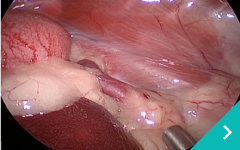

腹腔鏡下

門脈体循環シャント手術

副腎摘出術

胆嚢肝臓がん摘出手術